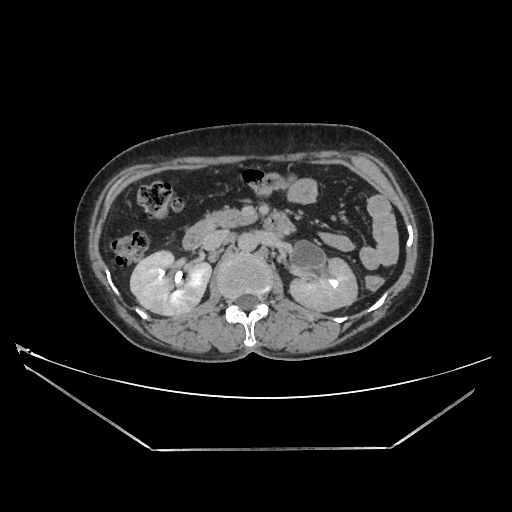

Urography images

A 50 years old woman with suffering from left sided PUJ obstruction